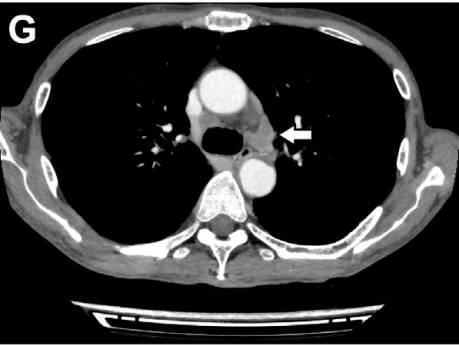

腹部CT增强扫描显示,纵膈淋巴结及肺门淋巴结肿大(图G、H)。